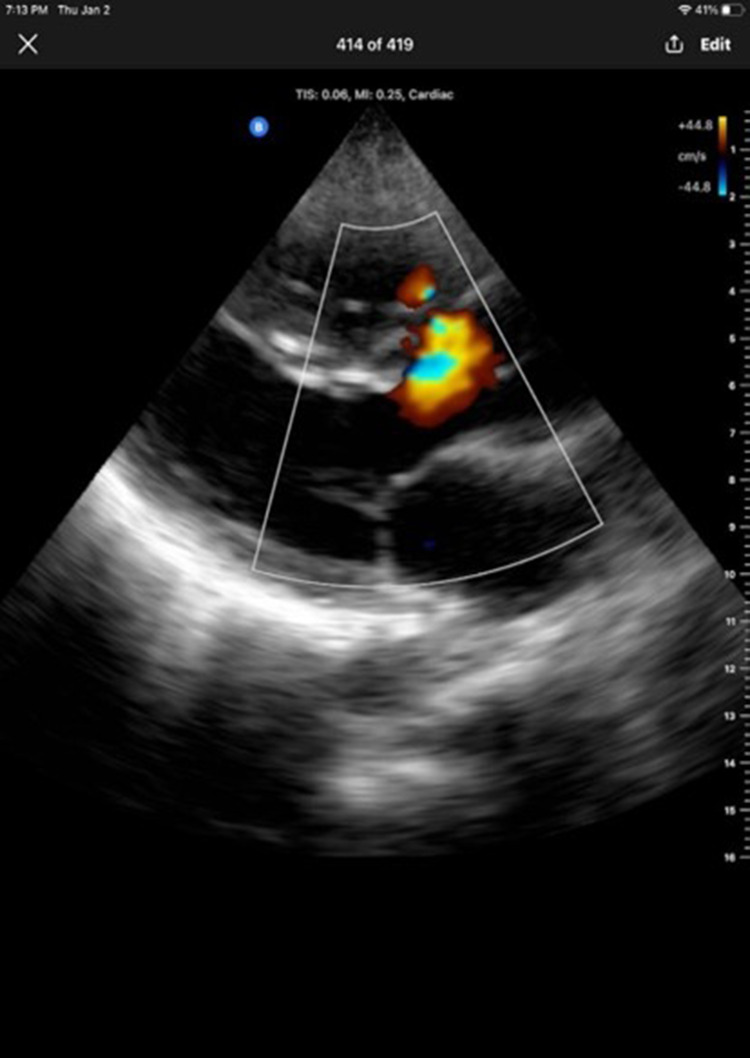

Case report: A 43-year-old male from Somalia presented with recurrent syncope, exertional dyspnea, and a history of congenital heart disease diagnosed in childhood. Due to financial constraints and limited healthcare access, he was unable to undergo surgery. On clinical examination, the patient exhibited cyanosis, grade 3 clubbing, and a pansystolic murmur. Investigations showed secondary polycythemia, right ventricular hypertrophy on ECG, and a large VSD with an overriding aorta. Echocardiography confirmed these findings, revealing the anatomical abnormalities typical of ToF.

Abstract Image